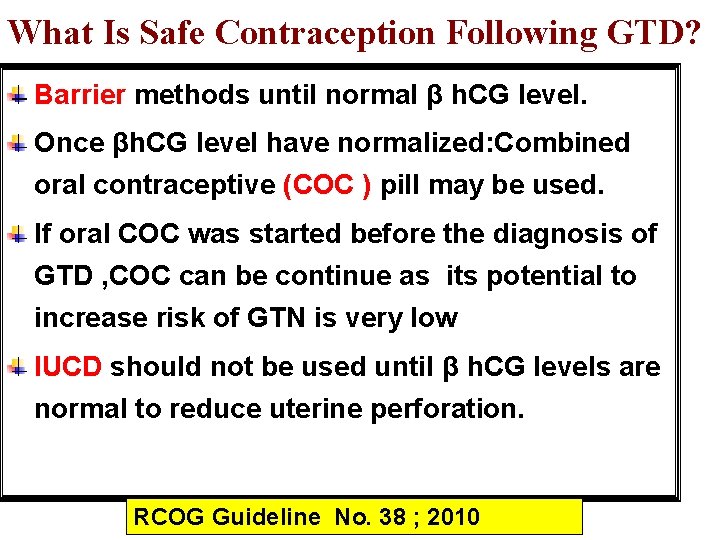

What Is Safe Contraception Following GTD? Barrier methods until normal β h. CG level. Once βh. CG level have normalized: Combined oral contraceptive (COC ) pill may be used. If oral COC was started before the diagnosis of GTD , COC can be continue as its potential to increase risk of GTN is very low IUCD should not be used until β h. CG levels are normal to reduce uterine perforation. RCOG Guideline No. 38 ; 2010